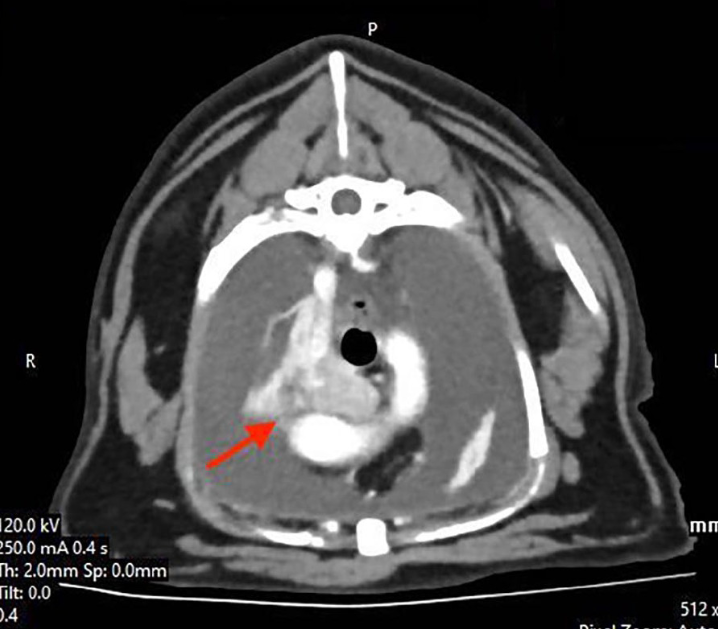

어쩌면 지금까지 거쳐온 수많은 유미흉, 흉수 고양이들이 이런 케모덱토마, 화학수용체종 이었을지도 모른다.

CT를 찍고, 수술까지 진행한 케이스이며

그 후 CT 진단후 31개월 후에 사망할때까지 추적검사를 진행한 증례이니 전반적인 흐름에 대한 기억을 위해 좋은 증례가 될것이니 심심할때 에세이 읽듯 꼭 읽어볼만 하다.